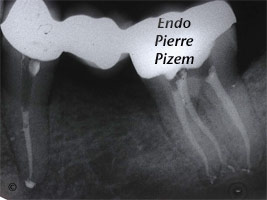

Long canaux en baïonnette sur une seconde molaire mandibulaire et traitement endodontique

Étude de cas numero: 6937 Longueur des canaux mésiaux: 25mm